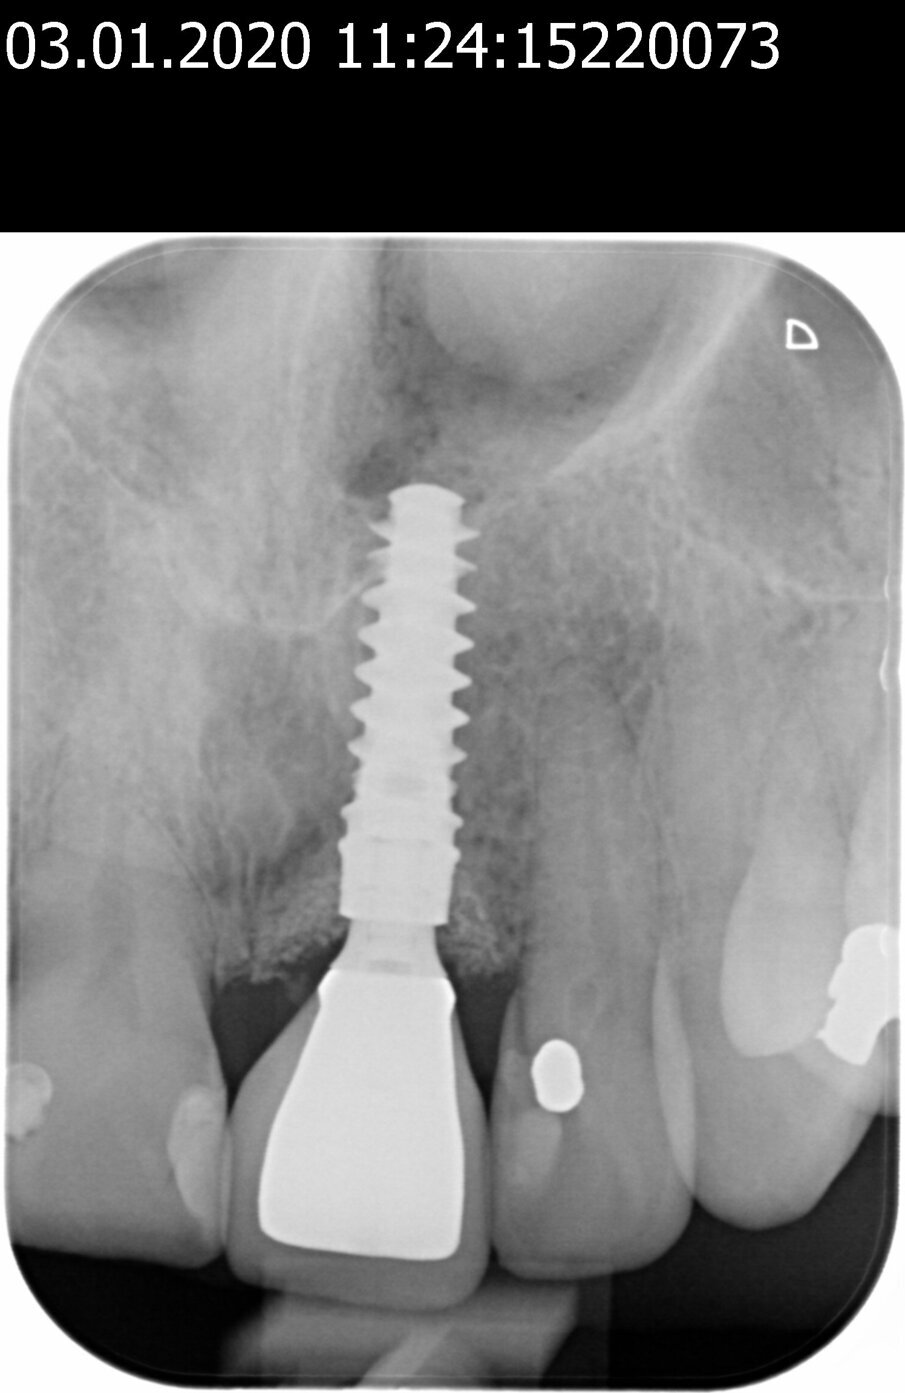

Una paziente di 53 anni si è presentata in studio con un incisivo sinistro fratturato a cui era stata più volte cementata una corona di ceramica (Figg. 1, 2). L’anamnesi e gli esami hanno evidenziato una buona salute sistemica e orale, un’occlusione ben equilibrata e nessuna abitudine al fumo. La tomografia cone beam (CBCT) e la radiografia periapicale hanno mostrato un riassorbimento radicolare esterno con inserimento nell’osso alveolare molto scarso, insufficiente per un adeguato posizionamento di un comune perno endocanalare (Figg. 3, 4). Considerando che il dente fratturato si trovava nella zona estetica, il paziente richiese un restauro nel modo più sicuro e più veloce possibile.

Fig. 3_Radiografia periapicale pre-operatoria.

Fig. 4_Scansione CBCT pre-operatoria.